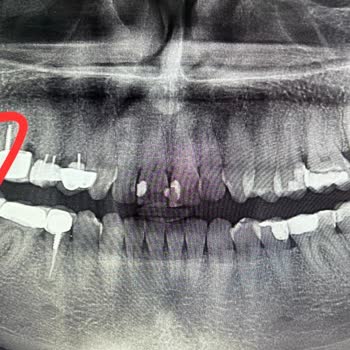

Dent Araz'da Çok Kötü Dolgu Yaptılar

Devrolduktan sonra çok bozuldu. Tecrübesi az doktorları çalıştırıyorlar. 1 Aralık 2023'te çıkan dolgumun yerine yenisini yaptırmaya gittim. En basit işlem. Yarım saatte zor yaptı, beni de kıvrandırdı. 1 hafta boyunca ağrı ve koku oldu. Çok kötü yapmış. Normal tüm dişlerin arası çizgi iken onun yaptı...